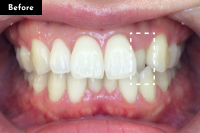

Basicプラン

上下前歯12本の部分矯正

20代 女性

治療費用:Basic 33万円(税込)

治療期間:4ヶ月

- Before

After